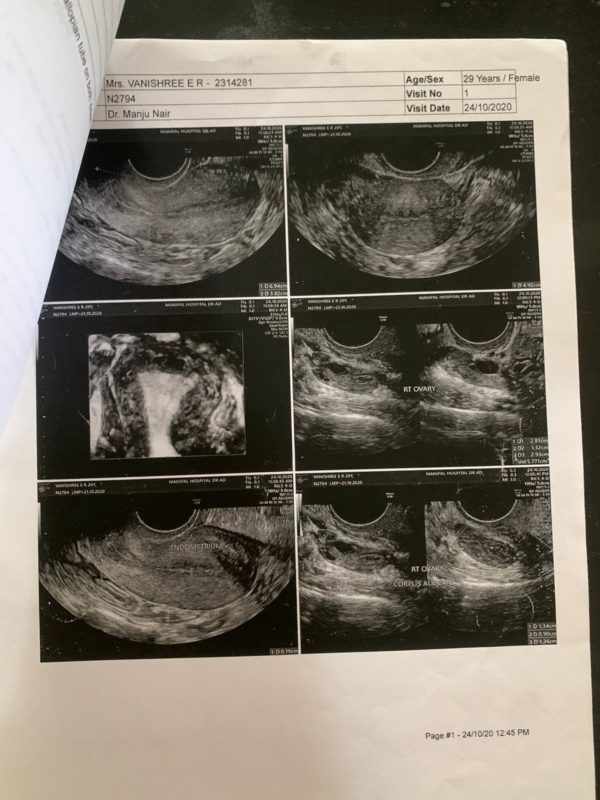

The images of the USG scan shows

1. Pre-

2. Post-

USG Reports

Pre – Right ovary showed a cyst with internal echoes suggestive of corpus albicans. Right side hydrosalphinx with chronic inflammation of the walls. Bilateral fallopian tube with inflamed walls. Left ovary appeared normal with a follicle